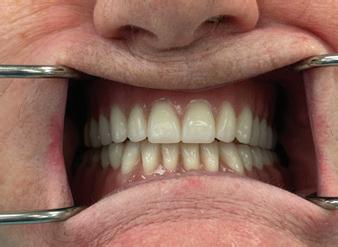

A 60-year-old female patient presented to the Oklahoma University College of Dentistry with the chief complaint, “My dogs chewed up my lower denture, and I need a replacement” (Figure 8a). Clinical examination revealed a completely edentulous oral cavity with advanced resorption of the mandibular alveolar ridge (Figure 1a and 1b). Based on panoramic radiographic ndings and nancial considerations, an implant-supported complete denture was determined to be impractical (Figure 2). A treatment plan was proposed involving the fabrication of a conventional maxillary complete denture and a mandibular complete denture using the neutral zone technique. As the maxillary denture was fabricated using conventional techniques, this report will primarily

Figure 1a. Maxillary ridge

Figure 1b. Resorbed mandibular ridge

e dentures were carefully evaluated and adjusted as necessary, with successful delivery demonstrated by the achievement of stability in the mandibular denture (Figure 8b).

Figure 7. Wax try-in

Figure 8a. Before

Figure 8b. After